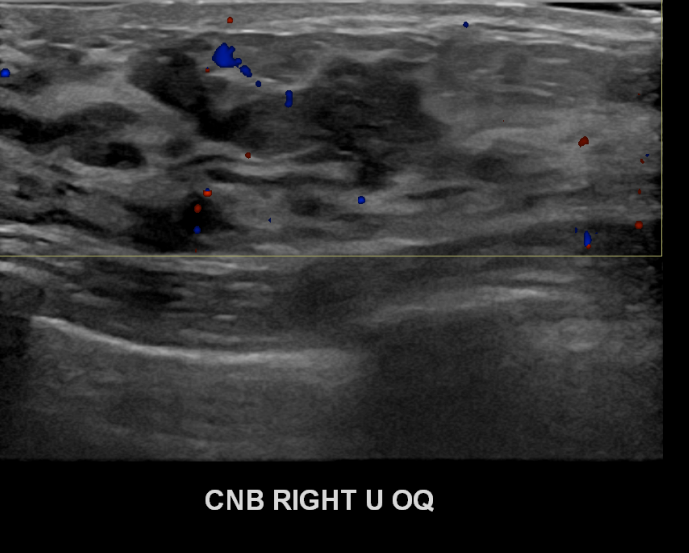

상기환자 우측유방에 딱딱한 멍울이만져져 내원하신 40대여성분으로 우측유방의 혹 조직검사시행후 유방암 진단되었습니다